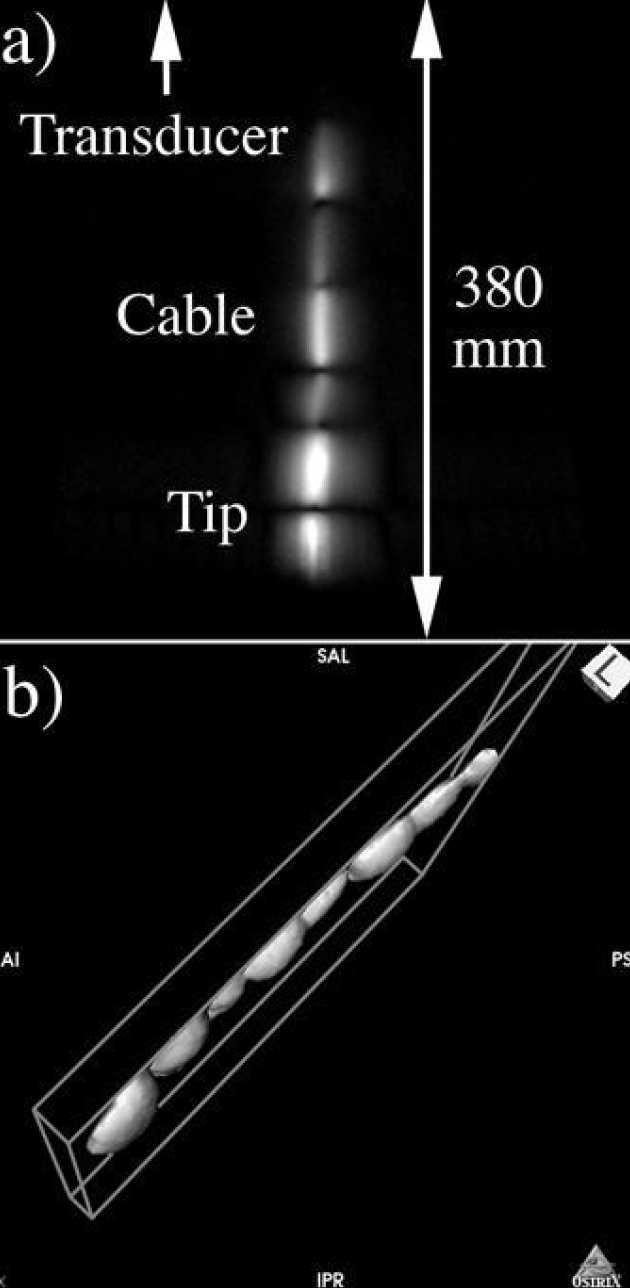

We have demonstrated a catheter-based RF receiver for internal magnetic resonance imaging is demonstrated. The device consists of a double-sided thin-film circuit, wrapped around a hollow catheter and sealed in place with heatshrink tubing. Signals are detected using a resonant L-C circuit at the catheter tip, and transmitted along the catheter using an array of coupled L-C circuits arranged as a magneto-inductive waveguide, a form of low frequency metamaterial. Coupling to a conventional RF system is accomplished using a demountable inductive transducer. Protection against external B1 and E fields is obtained by using figure-of-eight elements with an electrical length shorter than that of an immersed dipole. The system is primarily designed for biliary imaging, can pass the biopsy channel of a side-opening duodenoscope and is guidewire-compatible, potentially allowing clinicians to implement MR image guided procedures without changing their standard practice. Decoupling against B1 and E fields has been verified, and in vitro 1H magnetic resonance imaging with sub-mm resolution demonstrated at 1.5 T using phantoms.

|---|

| a) Stages in construction of catheter-based receiver; b) receiver with demountable transducer attached and passing into the biopsy channel of a non-magnetic duodenoscope; c) receiver passing from the side-port. |

|

|---|

| Axial 1H MR images obtained using a) an 8-element array and b) the catheter receiver; c) high-resolution image obtained using the catheter. |